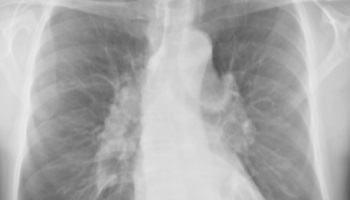

David, mon fils de 33 ans est atteint depuis sept ans d’une sarcoïdose, sous sa forme la plus sévère avec une atteinte pulmonaire provoquant une baisse importante de la capacité respiratoire.